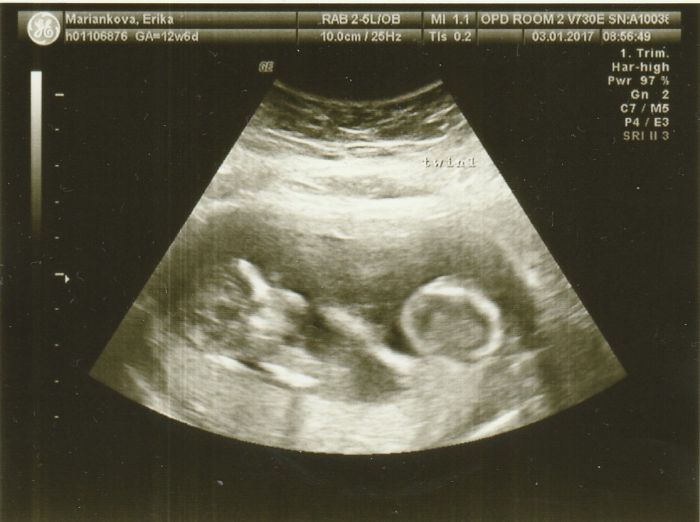

Ohlasujem sa po dlhsom case, nie ze by som nesledovala dianie sa tu ale to cakanie na prvy ultrazvuk a strach.... Takze dnes sme isli aj s drahym na prvy utz v Dubline. Ako som pisala do konca prveho trimestra tu oni nic neriesia, cize to 2 mesacne cakanie

. Podla tehotenskej kalkulacky som mala mat termin na 12.7, po dnesnom utz mi to upravili na 6.7a na moje prekvapenie su tam 2 fazulky

. Prvotny sok a moj drahy skoro nechal oci na obrazovke. Ale zato hned ako sme vysli z nemocnice tak zacal ze musime zacat vymyslat mena a hned radsej 4...2 chlapcenske a 2 dievcenske....uuuf tolko radostiiiiiii...len neviem ako to, lebo ani jeden nemame v rodine dvojcata. krasny vecer a pripajam aj foto...na 1 su obe fazulky a na druhej ten menej hamblivy, asi to bude chlapec